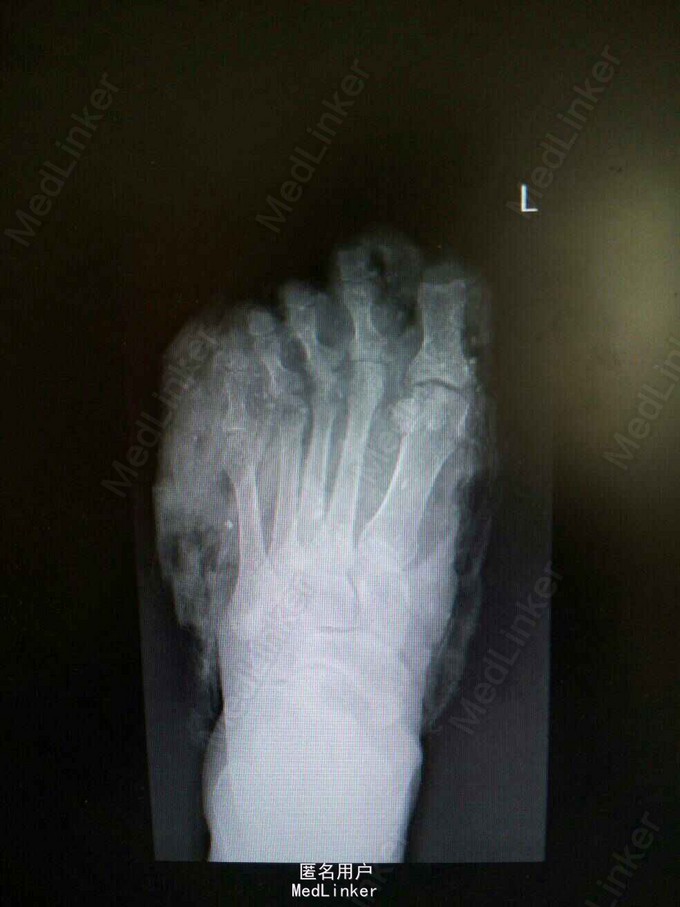

52岁女性患者,因“左足碾压撕脱伤4小时”入院。余病史无特殊。

查体:左足第1-4趾远节缺如,中、近节指骨完全外露,足背内侧、足底皮肤以及第5足趾向足底近端撕脱,足背外侧皮肤向足背近端撕脱,仅1cm宽皮肤相连,创面污染严重,大量砂石异物,足背动脉搏动可触及。辅助检查:左踝关节正侧位X线检查提示:左足各远节趾骨缺如;第二跖骨基底部撕脱性骨折;左足软组织肿胀以及软组织内异物。

诊断:左足碾压伤:第1-4趾远节缺损,第二跖骨基底部撕脱性骨折。 处理:急诊行左足清创+撕脱皮肤回植+第1-5趾截趾术+趾神经探查+足背动脉探查术,患者情况稳定后再次行左足清创,残端修整+VSD负压吸引术,而后行左足创面植皮。